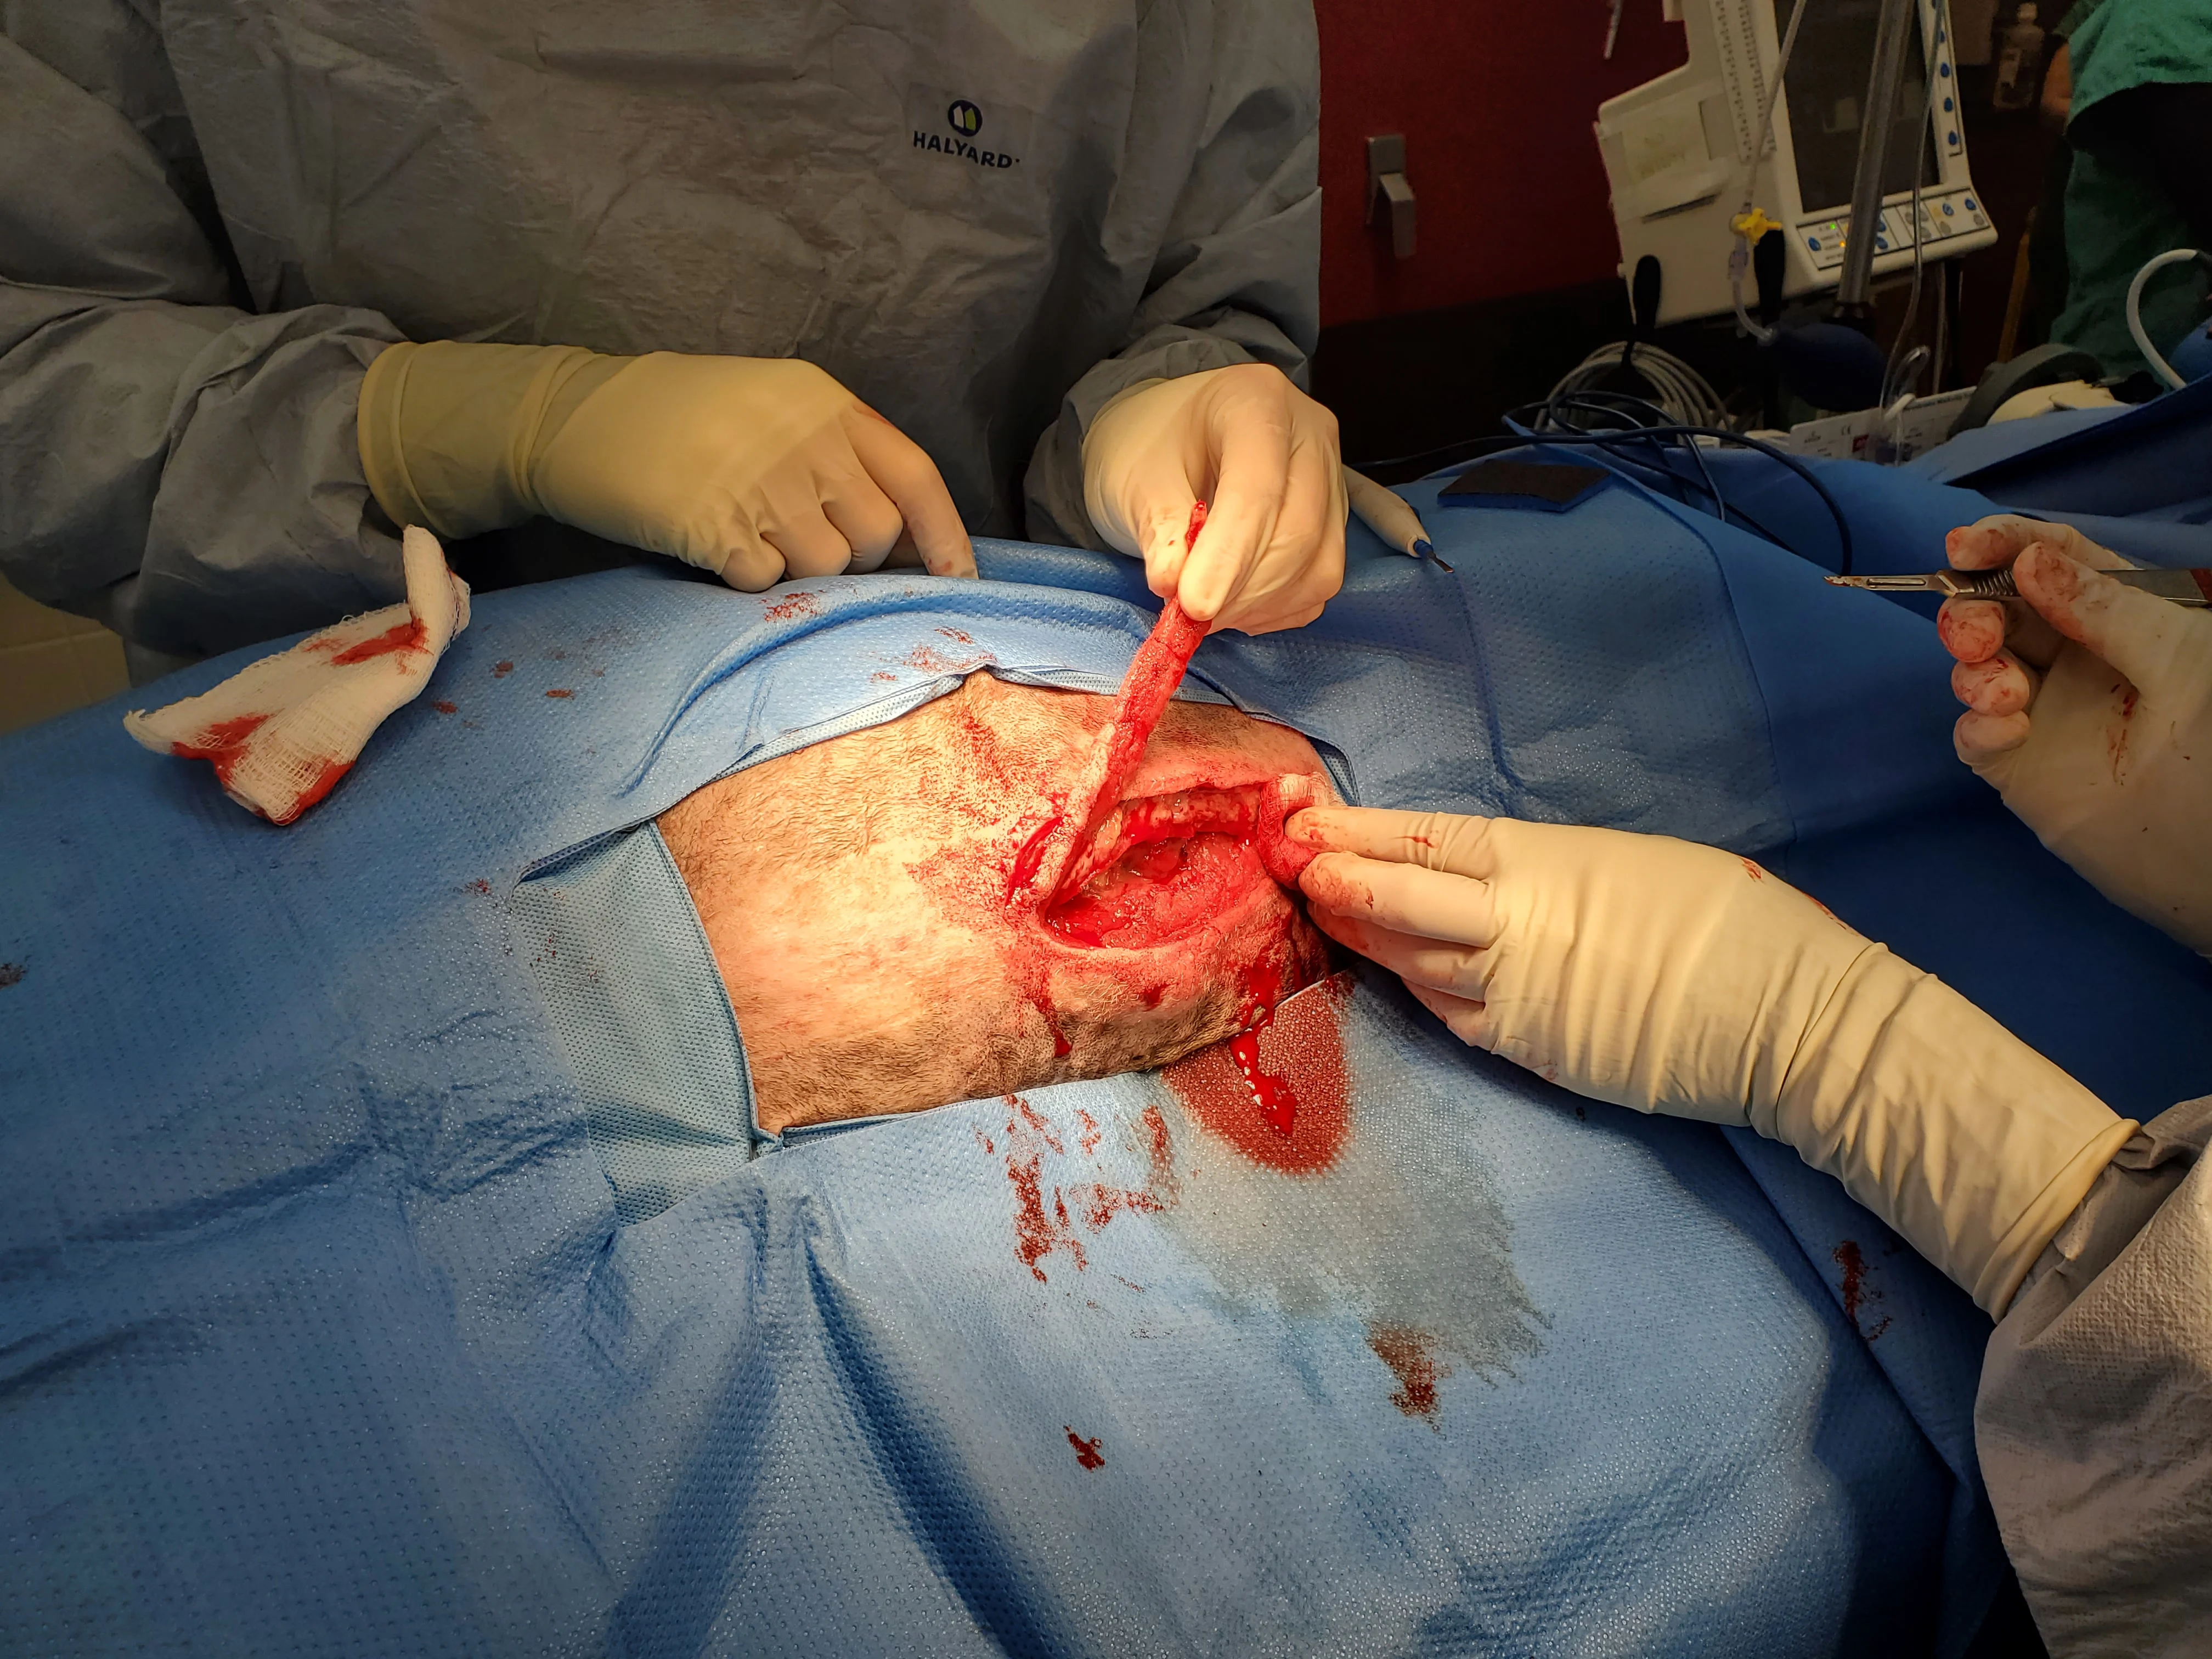

Figure 9 An obese (BCS, 9/9), 10-year-old neutered male American Staffordshire terrier was presented for incisional discharge 18 days after median sternotomy for thymoma removal, during which the sternebrae were reapposed with 0 and #1 polydioxanone suture in a figure-of-eight pattern. On presentation, serosanguinous fluid, cellulitis, and partial dehiscence were noted along the caudal extent of the incision. Thoracic radiographs and ultrasound were consistent with postoperative thoracotomy. The patient was anesthetized; fur around the wound was clipped; the wound was cleaned and surgically debrided; and tissue was collected for bacterial culture and susceptibility testing. A wide, loose continuous suture pattern of 0 polypropylene suture was placed in the skin, and a polyhexamethylene biguanide-impregnated gauze covered with medical-grade honey gel was inserted under the sutures, which were gently tightened to hold the dressing in place. The area was covered with sterile laparotomy pads held in place with an adhesive iodine-impregnated draping material. Ampicillin/sulbactam (30 mg/kg IV every 8 hours) was administered with the dog under anesthesia and continued overnight.

Closure-related complications of median sternotomy (eg, dehiscence, seroma, lameness, drainage, surgical site infections) are reported in 14% of dogs, with no significant difference between wire and suture closure, regardless of patient size.19